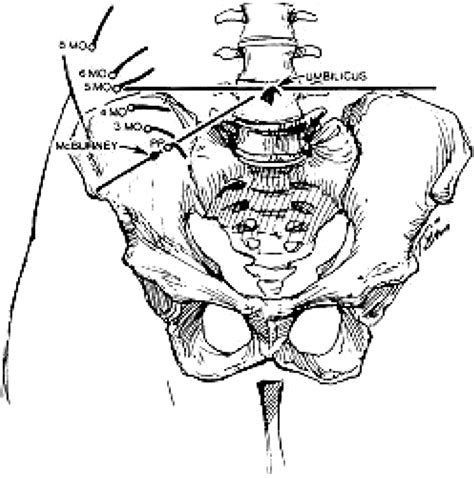

It is important to note that the location of the pain may shift as the pregnancy progresses. In the first trimester, the pain is usually in the lower right abdomen. However, as the uterus enlarges, the pain may be felt higher up in the abdomen.

• appendix location during pregnancy